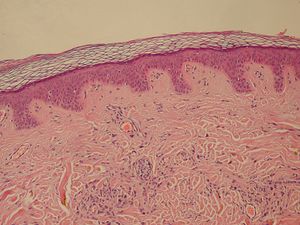

| Normal Epidermis and Dermis with Intradermal Nevus 10x-cropped | |

| خلايا ميلانينية | وحمة | |